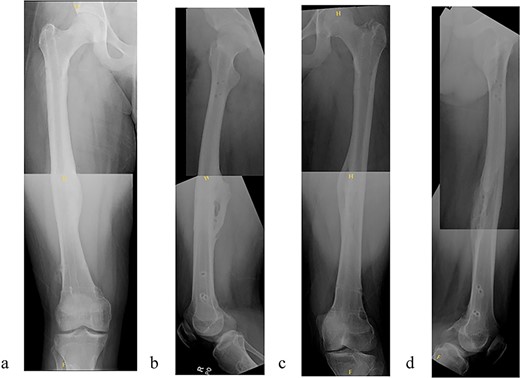

The patient tolerated the procedure well and recovered uneventfully. He was noted to have circumferential osseous healing at 1 year and underwent bilateral femur IMN removal 1.5 years postoperative without complication (Figs 4a–d and 5a–d).

(a) Right femur AP radiograph after implant removal. (b) Right femur lateral radiograph after implant removal. (c) Left femur AP radiograph after implant removal. (d) Left femur lateral radiograph after implant removal.